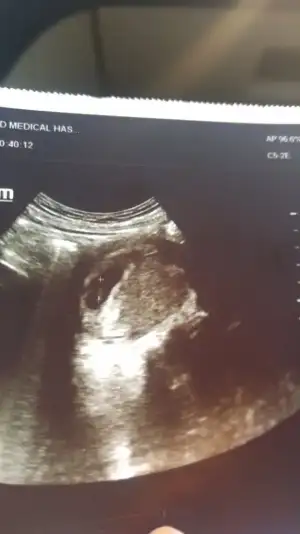

Kızlar ben minnoşumu gördümm kalbnide duydumm rabbm beklynn isteyen herkesse yaşatsnn çokk güzelll bir duyguymşş😍😍😍🙏🙏

Eklentiler

• 20200118_104712.webp

20200118_104712.webp

16,8 KB · Görüntüleme: 58